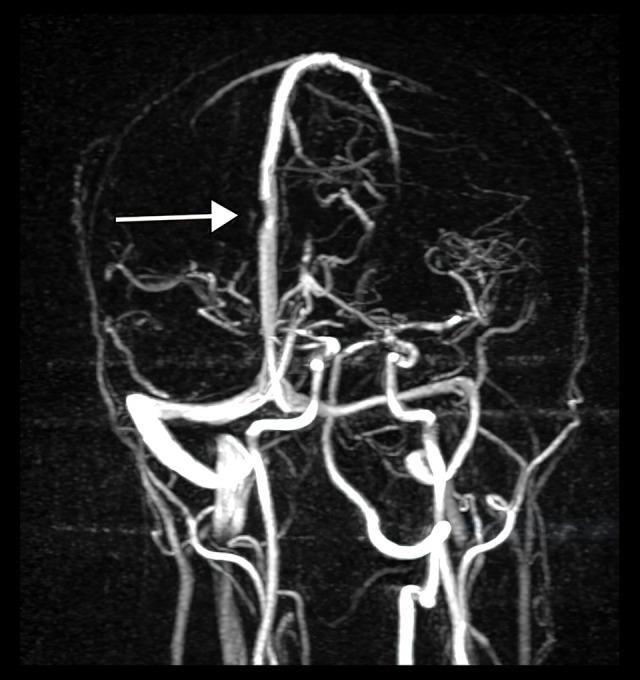

一名感染新型冠状病毒肺炎的48岁男性的脑浅表静脉血栓形成和脑内血肿:病例报告

Superficial Cerebral Venous Thrombosis and Intracerebral Hematoma in a 48-Year-Old Man with SARS-CoV-2 Infection: A Case Report.

BACKGROUND Pandemic coronavirus disease 2019 (COVID-19) originated in Wuhan, China, and is caused by severe acute respiratory syndrome coronavirus 2 (SARS-CoV-2). Severe respiratory symptoms are a hallmark of the disease, which may also include complications related to a hypercoagulable state and central nervous system involvement. These complications can occur during either the acute or the recovery phase. The cerebral involvement typically manifests as intracranial hypertension, intracerebral hemorrhage, diffuse encephalopathy, or cerebral venous thrombosis. The hemorrhagic form of cerebral venous thrombosis can be a diagnostic challenge and is treated by anticoagulation therapy, despite the existence of an intracerebral hemorrhage. This report describes a case of superficial cerebral venous thrombosis and intracerebral hematoma in a 48-year-old man weeks after recovering from the acute phase of SARSCoV-2 infection. CASE REPORT A 48-year-old man with a past medical history of SARS-CoV-2 infection confirmed by SARS-CoV-2 reverse-transcription polymerase chain reaction presented with left upper-limb numbness, weakness, and impaired positional sensorium. After initial stabilization, noncontrast computerized tomography and magnetic resonance imaging confirmed an intracerebral hemorrhage with underlying cerebral venous thrombosis. The patient was successfully treated with enoxaparin anticoagulation therapy, and symptoms improved over the following 12 days. CONCLUSIONS Central nervous system venous thrombosis is an atypical presentation of the hypercoagulable state primarily seen in younger patients, and it can occur in a delayed fashion after recovery from mild forms of COVID-19.

背景 2019 年冠状病毒病大流行(COVID-19)起源于中国武汉,由严重急性呼吸综合征冠状病毒 2(SARS-CoV-2)引起。严重的呼吸道症状是该疾病的一个标志,其还可能包括与高凝状态和中枢神经系统受累相关的并发症。这些并发症可发生在急性期或恢复期。脑部受累通常表现为颅内高压、脑出血、弥漫性脑病或脑静脉血栓形成。脑静脉血栓形成的出血形式可能是一个诊断难题,尽管存在脑出血,但仍通过抗凝治疗。本报告描述了一名 48 岁男性在从 SARS-CoV-2 感染急性期康复数周后发生浅表性脑静脉血栓形成和脑内血肿的病例。病例报告 一名有 SARS-CoV-2 逆转录聚合酶链反应确诊的 SARS-CoV-2 感染病史的 48 岁男性,出现左上肢麻木、无力和位置感觉受损。在初步稳定后,非增强计算机断层扫描和磁共振成像证实为伴有潜在脑静脉血栓形成的脑出血。该患者接受依诺肝素抗凝治疗成功,症状在接下来的 12 天内有所改善。结论 中枢神经系统静脉血栓形成是高凝状态的一种非典型表现,主要见于年轻患者,并且可在从轻度 COVID-19 康复后延迟发生。